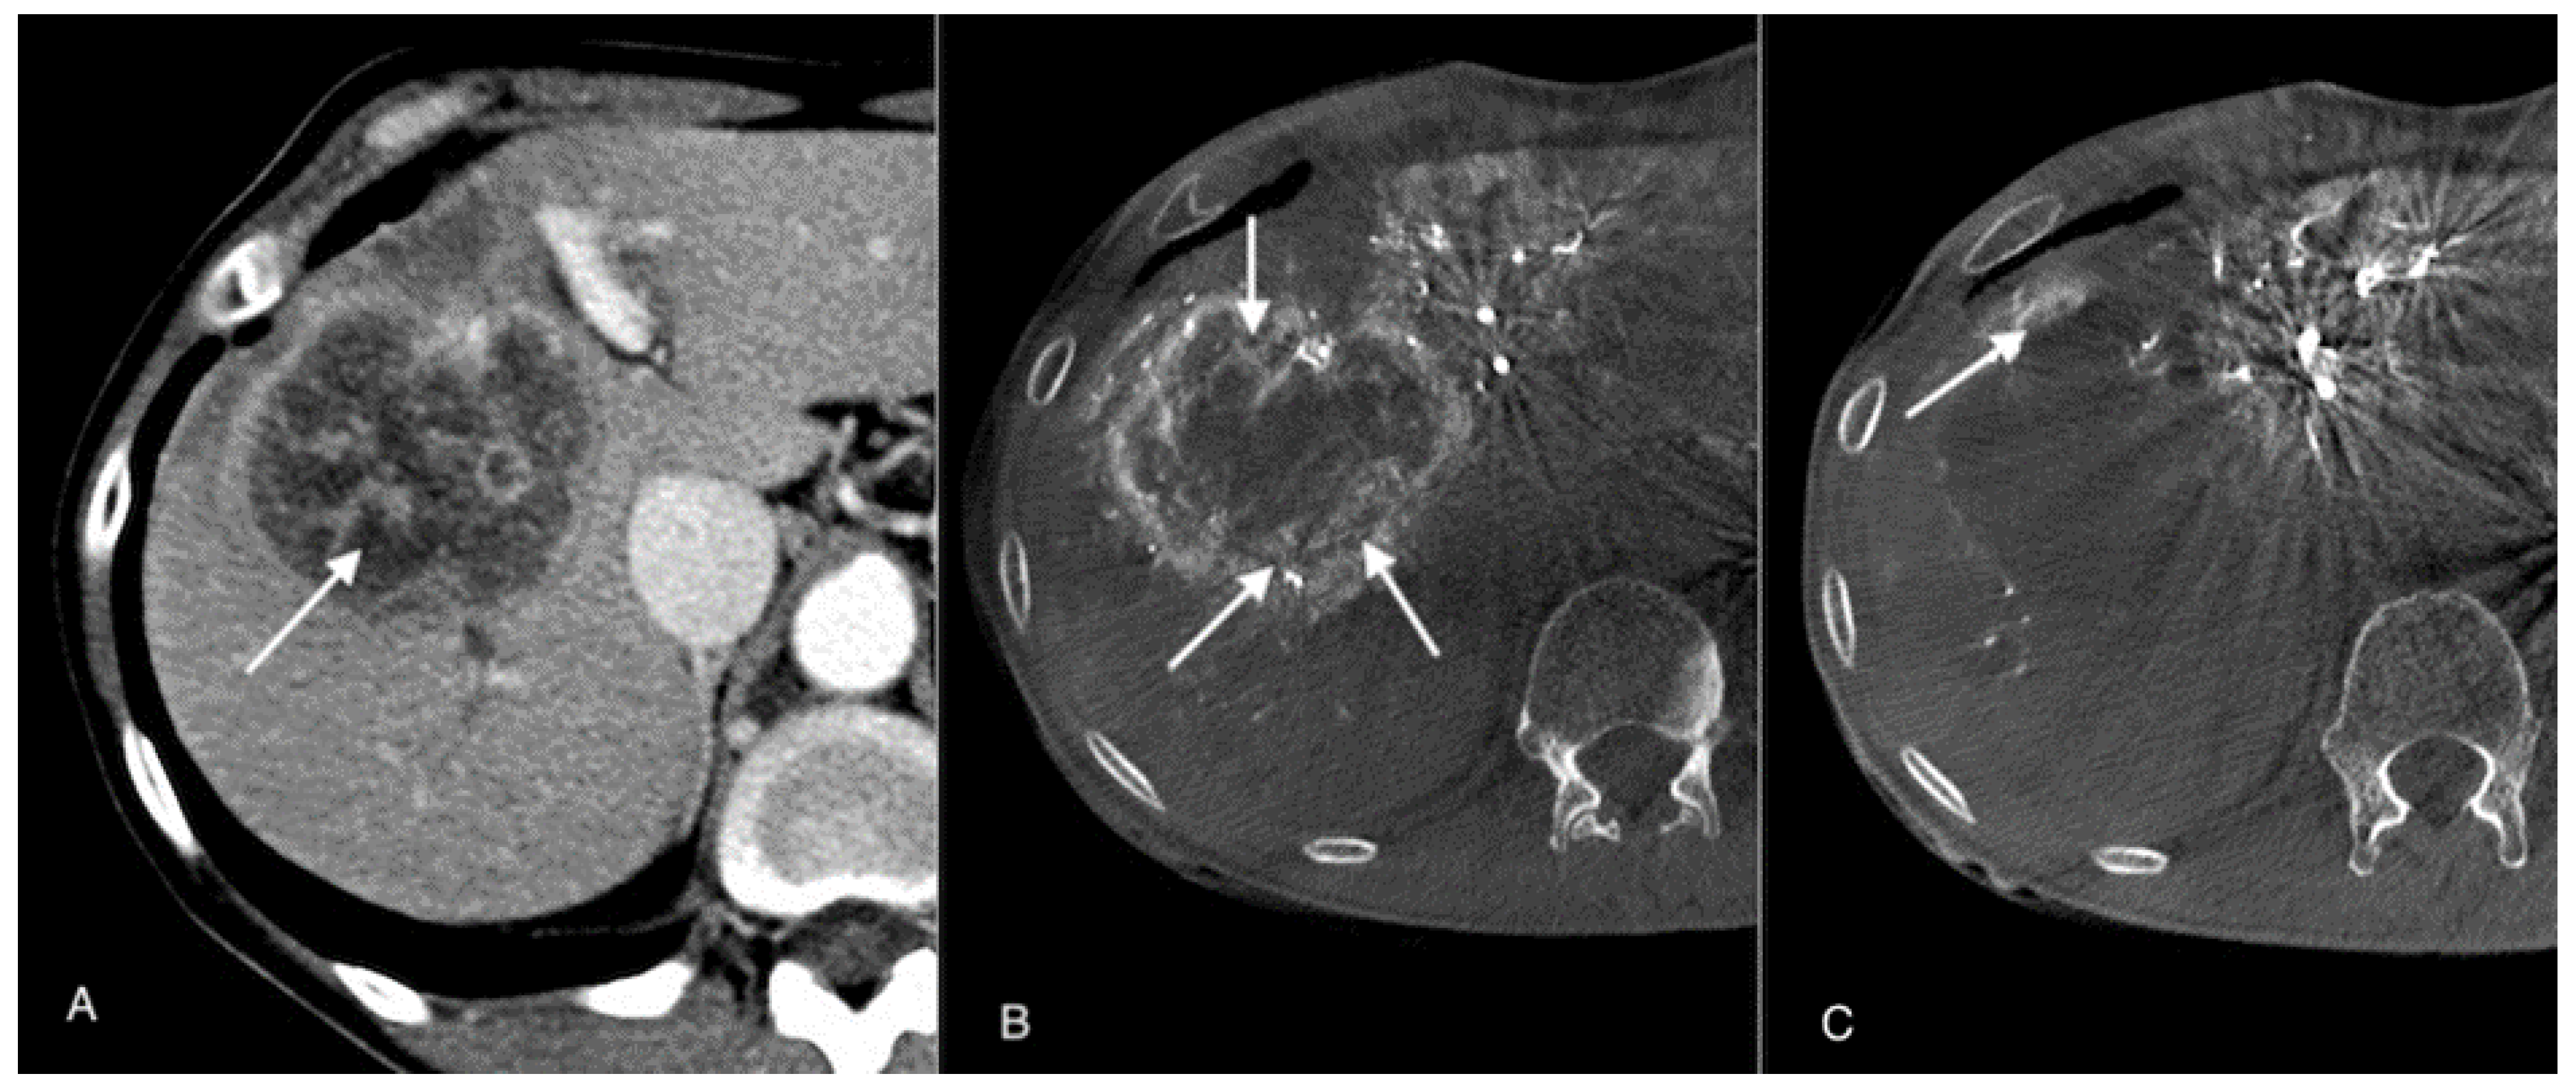

2.4. Imaging and Tumor Response

3.2. Radiological Response after TACE